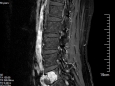

擅长: 颈腰椎退变性疾病、脊柱骨折、脊柱肿瘤﹑脊柱畸形矫形以及脊柱结核的治疗,尤其以脊柱肿瘤﹑脊柱感染、脊柱畸形的手术治疗,和采用先进微创﹑内镜技术治疗颈腰椎椎间盘突出等退变性疾病知名。

四川大学华西医学中心研究生毕业,硕士研究生导师,四川省人民医院骨科脊柱组组长,从事脊柱外科临床工作20余年,成功开展数千例脊柱手术,曾多次到国内外著名脊柱外科中心交流学习。擅长颈腰椎退变性疾病、脊柱骨折、脊柱肿瘤、脊柱畸形矫形以及脊柱感染的治疗,尤其脊柱肿瘤﹑脊柱感染、脊柱畸形的手术治疗和采用先进微创﹑内镜技术治疗颈腰椎椎间盘突出等退变性疾病。

攻克脊柱外科“手术禁区”,我院骨科成功实施高难度腰5椎体全切术